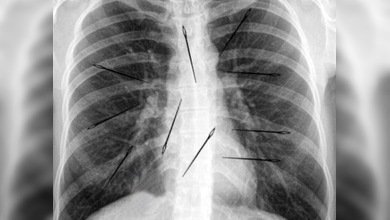

Más de 20 agujas en el cuerpo de una mujer brasileña fueran descubiertas por médicos del estado brasileño de Pará en la Amazonia, informan medios locales. La mujer, de 35 años, visitó al médico con quejas de dolor de oído y las agujas fueron encontradas casualmente a través de una radiografía de tórax. El examen médico mostró que en su cuerpo se encontraban entre 24 a 26 agujas de acero en sus tejidos blandos.

Próximamente una junta médica tendrá que decidir si hace falta una intervención quirúrgica para extraer los cuerpos extraños. Según datos recabados, la mujer nació en la familia de una costurera y en su infancia tenía libre a agujas, las que solía introducir en su cuerpo cuando tenía entre 9 y 11 años. Lo insólito del caso es que la misma paciente no se acuerda de esto y nunca jamás se ha quejado de dolor en estos 20 años.